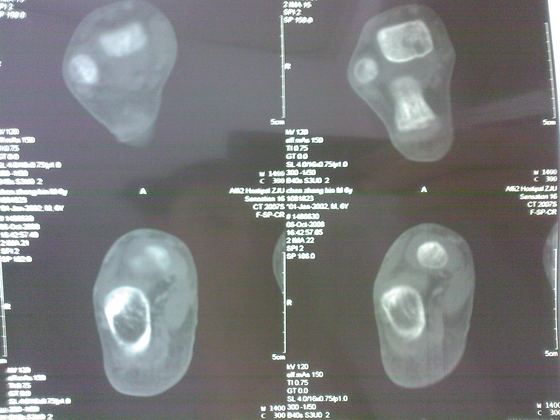

把病理送浙一医会诊后诊断为:骨外软骨瘤。同时做了CT检查。暂未予治疗。

今天把创面情况跟CT发上请大家看看。

继续发CT片

继续还有几张。